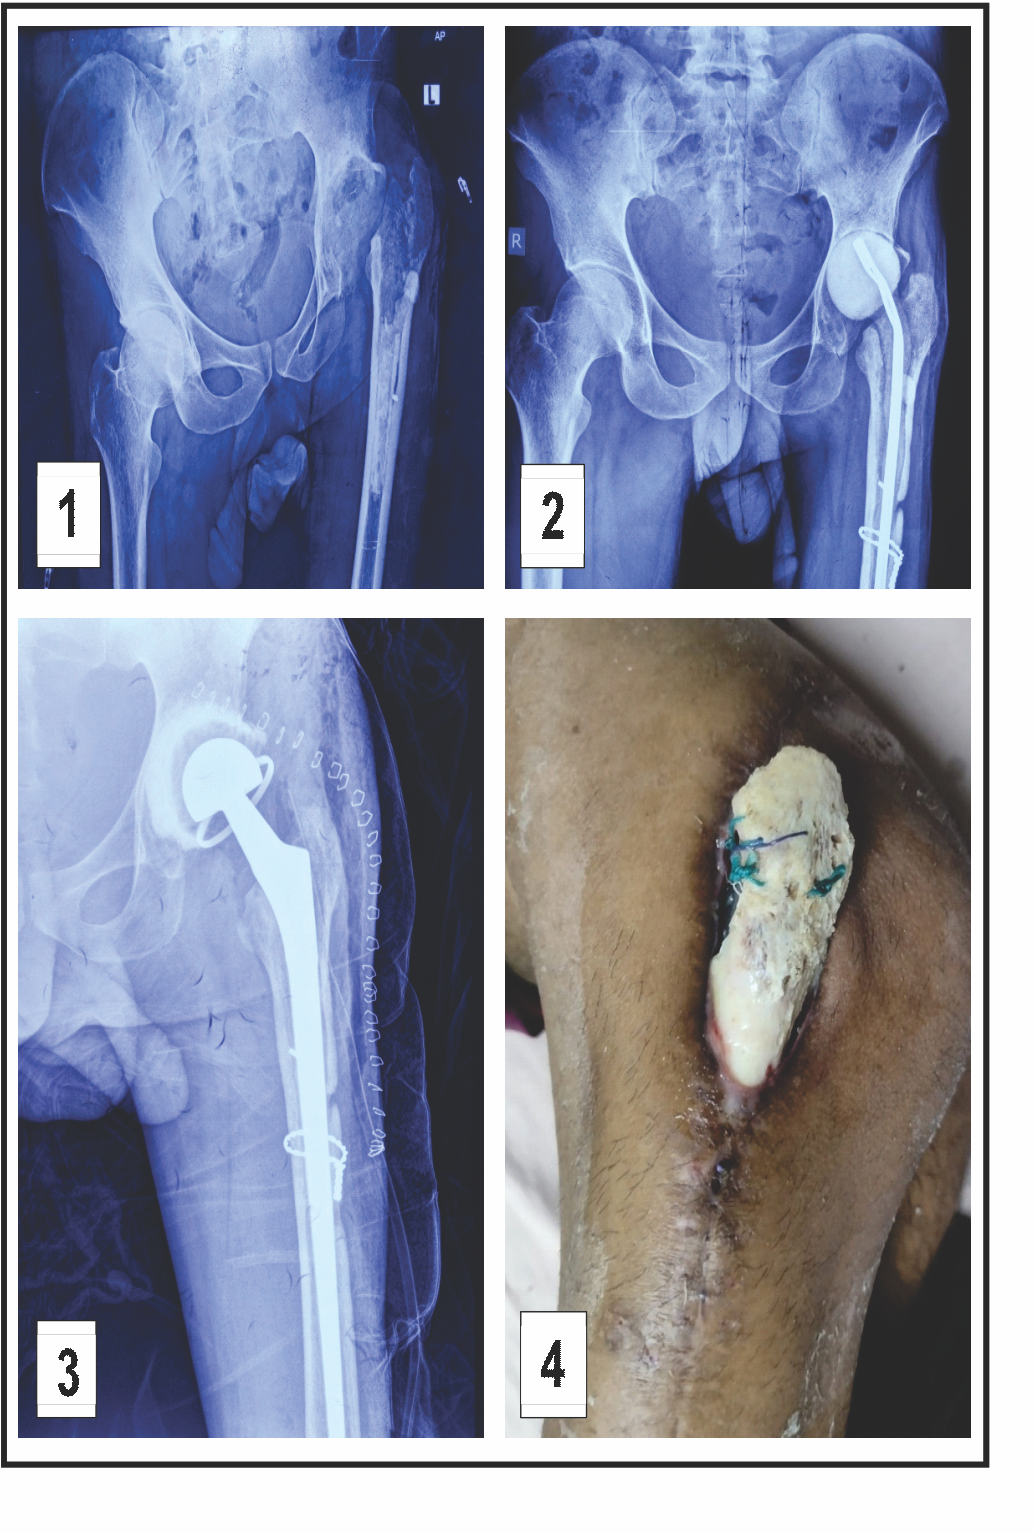

A 37-year-old male patient with hepatitis C presented with a persistent sinus tract at the surgical site following implant removal for an infected THA. The patient had undergone total hip replacement 4 years ago, which subsequently got infected. Implant removal was done 1 year back. Radiographs showing the left hip status after implant removal are shown in Fig. 1. At presentation, C-reactive protein (CRP), erythrocyte sedimentation rate (ESR), and total leukocyte count were 56 mg/L, 78 mm/h, and 14,700 cells/mm3, respectively. A two-stage revision was planned, and the risks and benefits were discussed with the patient.

Stage 1 involved surgical site debridement, antibiotic spacer placement, and initiation of intravenous antibiotics. Culture report revealed methicillin-resistant Staphylococcus aureus, sensitive to vancomycin, which was continued for 6 weeks. Fig. 2 displays hip radiographs with the antibiotic spacer in situ. Two weeks after completing antibiotic treatment, CRP levels normalized.

Stage 2 included removal of the antibiotic spacer and implantation of a new prosthesis (Fig. 3). Due to the absence of identifiable abductor musculature intraoperatively, a constrained acetabular cup was utilized. The 1st post-operative week was uneventful. However, by the end of the 2nd post-operative week, the surgical site dehisced with purulent discharge. Subsequently, the entire greater trochanter became exposed and devitalized, with concurrent exposure of the trunnion (Fig. 4). In consultation with a plastic surgeon, the decision was made to proceed with DAIR and flap coverage. All devitalized bone was debrided until healthy bleeding points were observed (Fig. 5). Simultaneously, a musculocutaneous anterolateral thigh flap was raised and inset by the plastic surgery team (Fig. 6). Multiple drains were placed. Postoperatively, the patient received intravenous piperacillin-tazobactam and linezolid for 6 weeks. Culture of intraoperative samples was negative. Sutures were removed on post-operative day 14. The patient was advised to remain on non-weight-bearing mobilization from post-operative day 2. Hip range-of-motion exercises and partial weight-bearing ambulation were initiated during the 3rd post-operative week, progressing to full weight-bearing by the 6th week. At the 3-month follow-up, the flap had healed successfully (Fig. 7). Inflammatory markers at that time were CRP 4.1 mg/L and ESR 28 mm/h. Post-operative radiographs were obtained at 6 weeks, 6 months, and 12 months (Fig. 8). At the most recent follow-up (12 months), the patient was ambulant with walker support and doing well clinically.